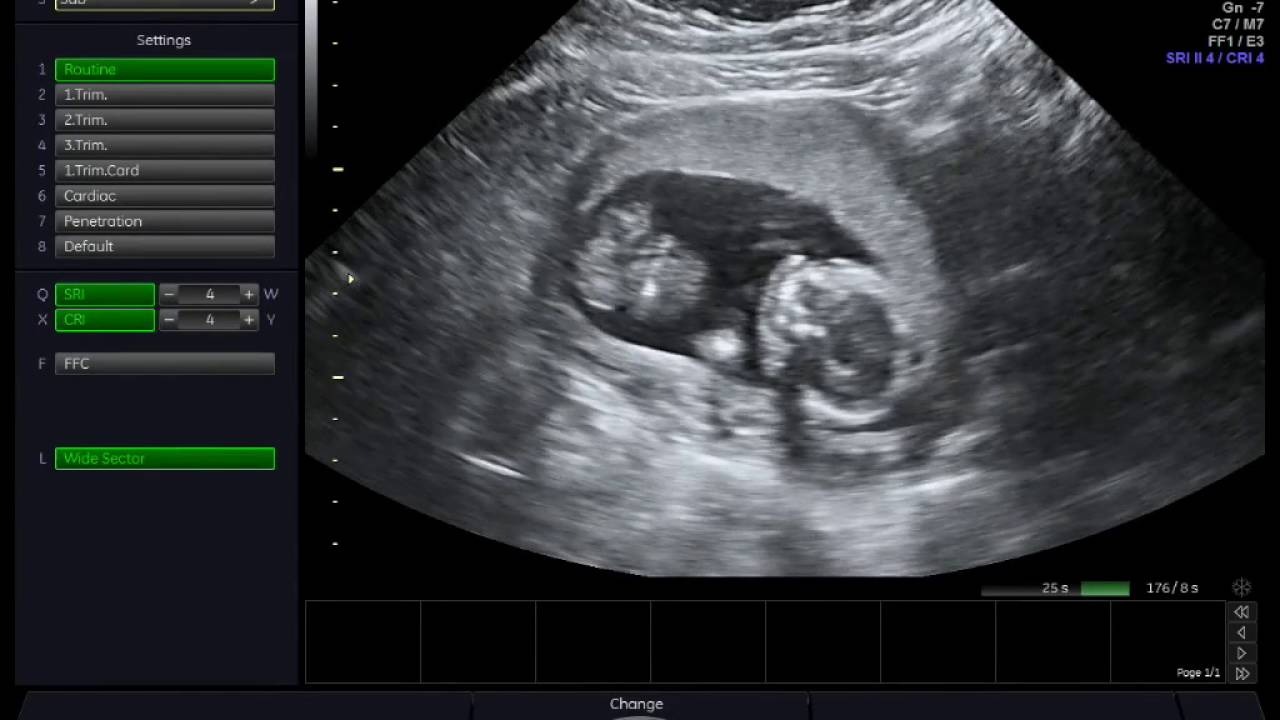

Tuần thứ 16 là giai đoạn thai nhi trong bụng bắt đầu phát triển tốt hơn. Các bộ phận như xương, móng tay, móng chân dần được hoàn thiện và cứng cáp. Khi đi siêu âm, mẹ bầu 16 tuần có thể thấy được nhiều sự thay đổi của con. Điển hình như:

Kích thước lớn dần: Lúc này, thai nhi có thể dài khoảng 12cm, nặng khoảng 100g. Tim thai sẽ hoạt động mạnh mẽ, bơm 25 lít máu nuôi dưỡng cơ thể. Và lượng máu này có thể tăng theo thời gian.

Tay chân cử động nhiều hơn: Do xương đã phát triển, cứng cáp hơn, các phản xạ của tay chân và cơ thể cũng được hình thành

Mắt của thai cũng di chuyển: Đây là thời điểm mắt di chuyển tới mặt trước của đầu. Hơn nữa, cho dù mí mắt chưa mở nhưng mắt vẫn có thể tới bên này, bên kia.

Tai về đúng vị trí: Tai sẽ về vị trí và bắt đầu lắng nghe được giọng nói của con người và những tiếng ồn xung quanh.

Biểu cảm: Khuôn mặt sẽ có những biểu cảm nhất định, đôi khi sẽ có hành động ngáp ngủ cực đáng yêu. Đây cũng chính là khoảnh khắc hạnh phúc nhất của người phụ nữ khi đi siêu âm.